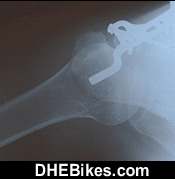

Downhill Dave's left leg x-ray after surgery. This was a massive tibial plateau fracture and the Kamlopps Surgeon stopped counting at 20 fractures. He said he was considering amputating during surgery and told me I'd likely never walk on it again.

The titanium hardware consists of 12 bolts/ screws and the one big side plate.

After incredibly intense therapy and training, I was actually able to make a pretty full recovery and got back to racing 2 years after this 1998 crash at the National Downhill Mountain Bike Championships at Sun Peaks Ski Resort. 2 years after the injury, I was actually faster on the same race tracks than before the injury.

This injury is the main reason for me building my Downhill Electric Mountain Bike as the pain is constant and terrible and is worse when I press down on the pedals like when climbing.